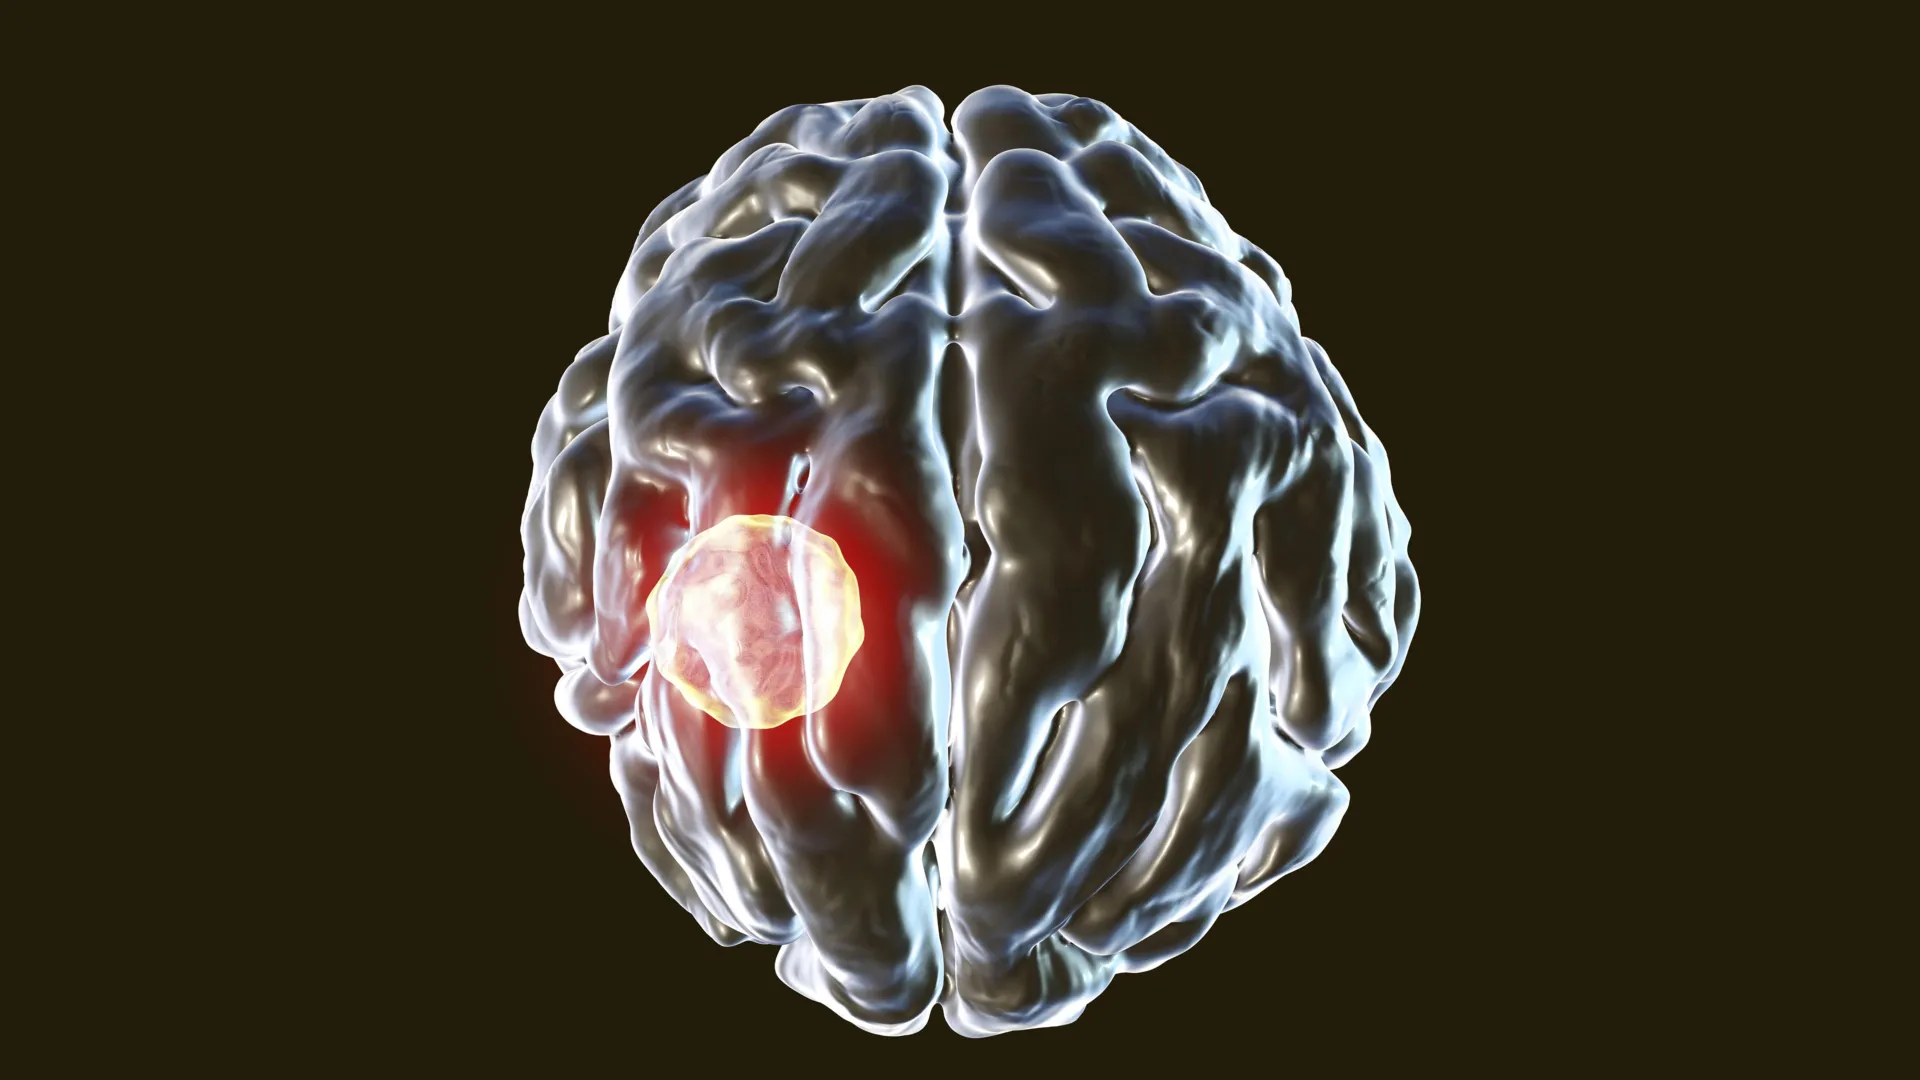

The ubiquitous nature of Toxoplasma gondii stems from its widespread distribution among warm-blooded animals, including humans, and its varied transmission routes. Exposure commonly occurs through direct contact with domestic cats, definitive hosts for the parasite, or via the ingestion of undercooked meat, unwashed produce, or contaminated water. Once it breaches the body’s defenses, Toxoplasma gondii embarks on a migratory journey, potentially affecting multiple organ systems before establishing a chronic, lifelong residency within the brain. The disease it causes, toxoplasmosis, typically presents a mild or asymptomatic course in immunocompetent individuals. However, for those with compromised immune systems, such as organ transplant recipients or individuals with HIV/AIDS, the infection can escalate into severe, life-threatening conditions, leading to neurological disorders, ocular inflammation, and even fetal damage in cases of congenital transmission.

Central to this cellular self-termination process is a critical enzyme known as caspase-8. The research team identified caspase-8 as the linchpin in the CD8+ T cells’ ability to control T. gondii infection. This enzyme plays a pivotal role in orchestrating programmed cell death, a highly regulated process essential for maintaining tissue homeostasis and eliminating damaged or infected cells. In a series of meticulously designed experiments utilizing murine models, the researchers observed a stark contrast in the parasitic burden within the brains of mice engineered to lack caspase-8 in their T cells compared to their healthy counterparts. Despite both groups mounting robust immune responses to the initial infection, the mice deficient in caspase-8 exhibited significantly higher levels of T. gondii in their brains, ultimately succumbing to severe illness and mortality.

Conversely, mice with functional caspase-8 within their T cells managed to maintain the infection at significantly lower levels, remaining healthy. Histopathological examination of brain tissue from these mice revealed that their CD8+ T cells were far less likely to be harboring the parasite. This compelling evidence strongly suggests that caspase-8 is not merely an accessory player but a vital component in limiting the intracellular proliferation of T. gondii within T cells. Furthermore, these findings contribute to a growing body of scientific literature underscoring the broad significance of caspase-8 in the body’s defense against a diverse array of infectious agents.